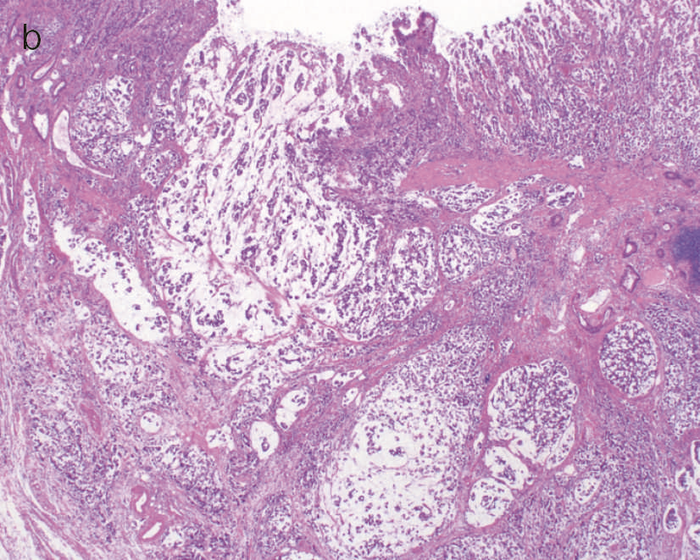

- 内腔狭窄を伴った5型の腫瘍(矢印)を認める。

- 組織学的には,粘液癌あるいは低分化腺癌が壁内に浸潤している像を認める。